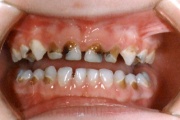

Hambakaaries

Lutipudelikaariese kahjustused

Lutipudelikaaries